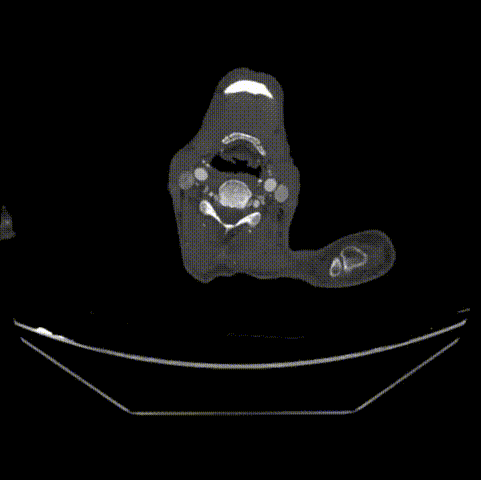

CTA提示患者主动脉弓型为Ⅲ型弓,左侧椎动脉为优势动脉,夹层累及至双侧髂外动脉,腹腔干动脉,肠系膜上动脉及左肾动脉为真腔供血,右肾动脉为真假腔供血,左侧胸腔少量积液。

远端真腔长轴直径